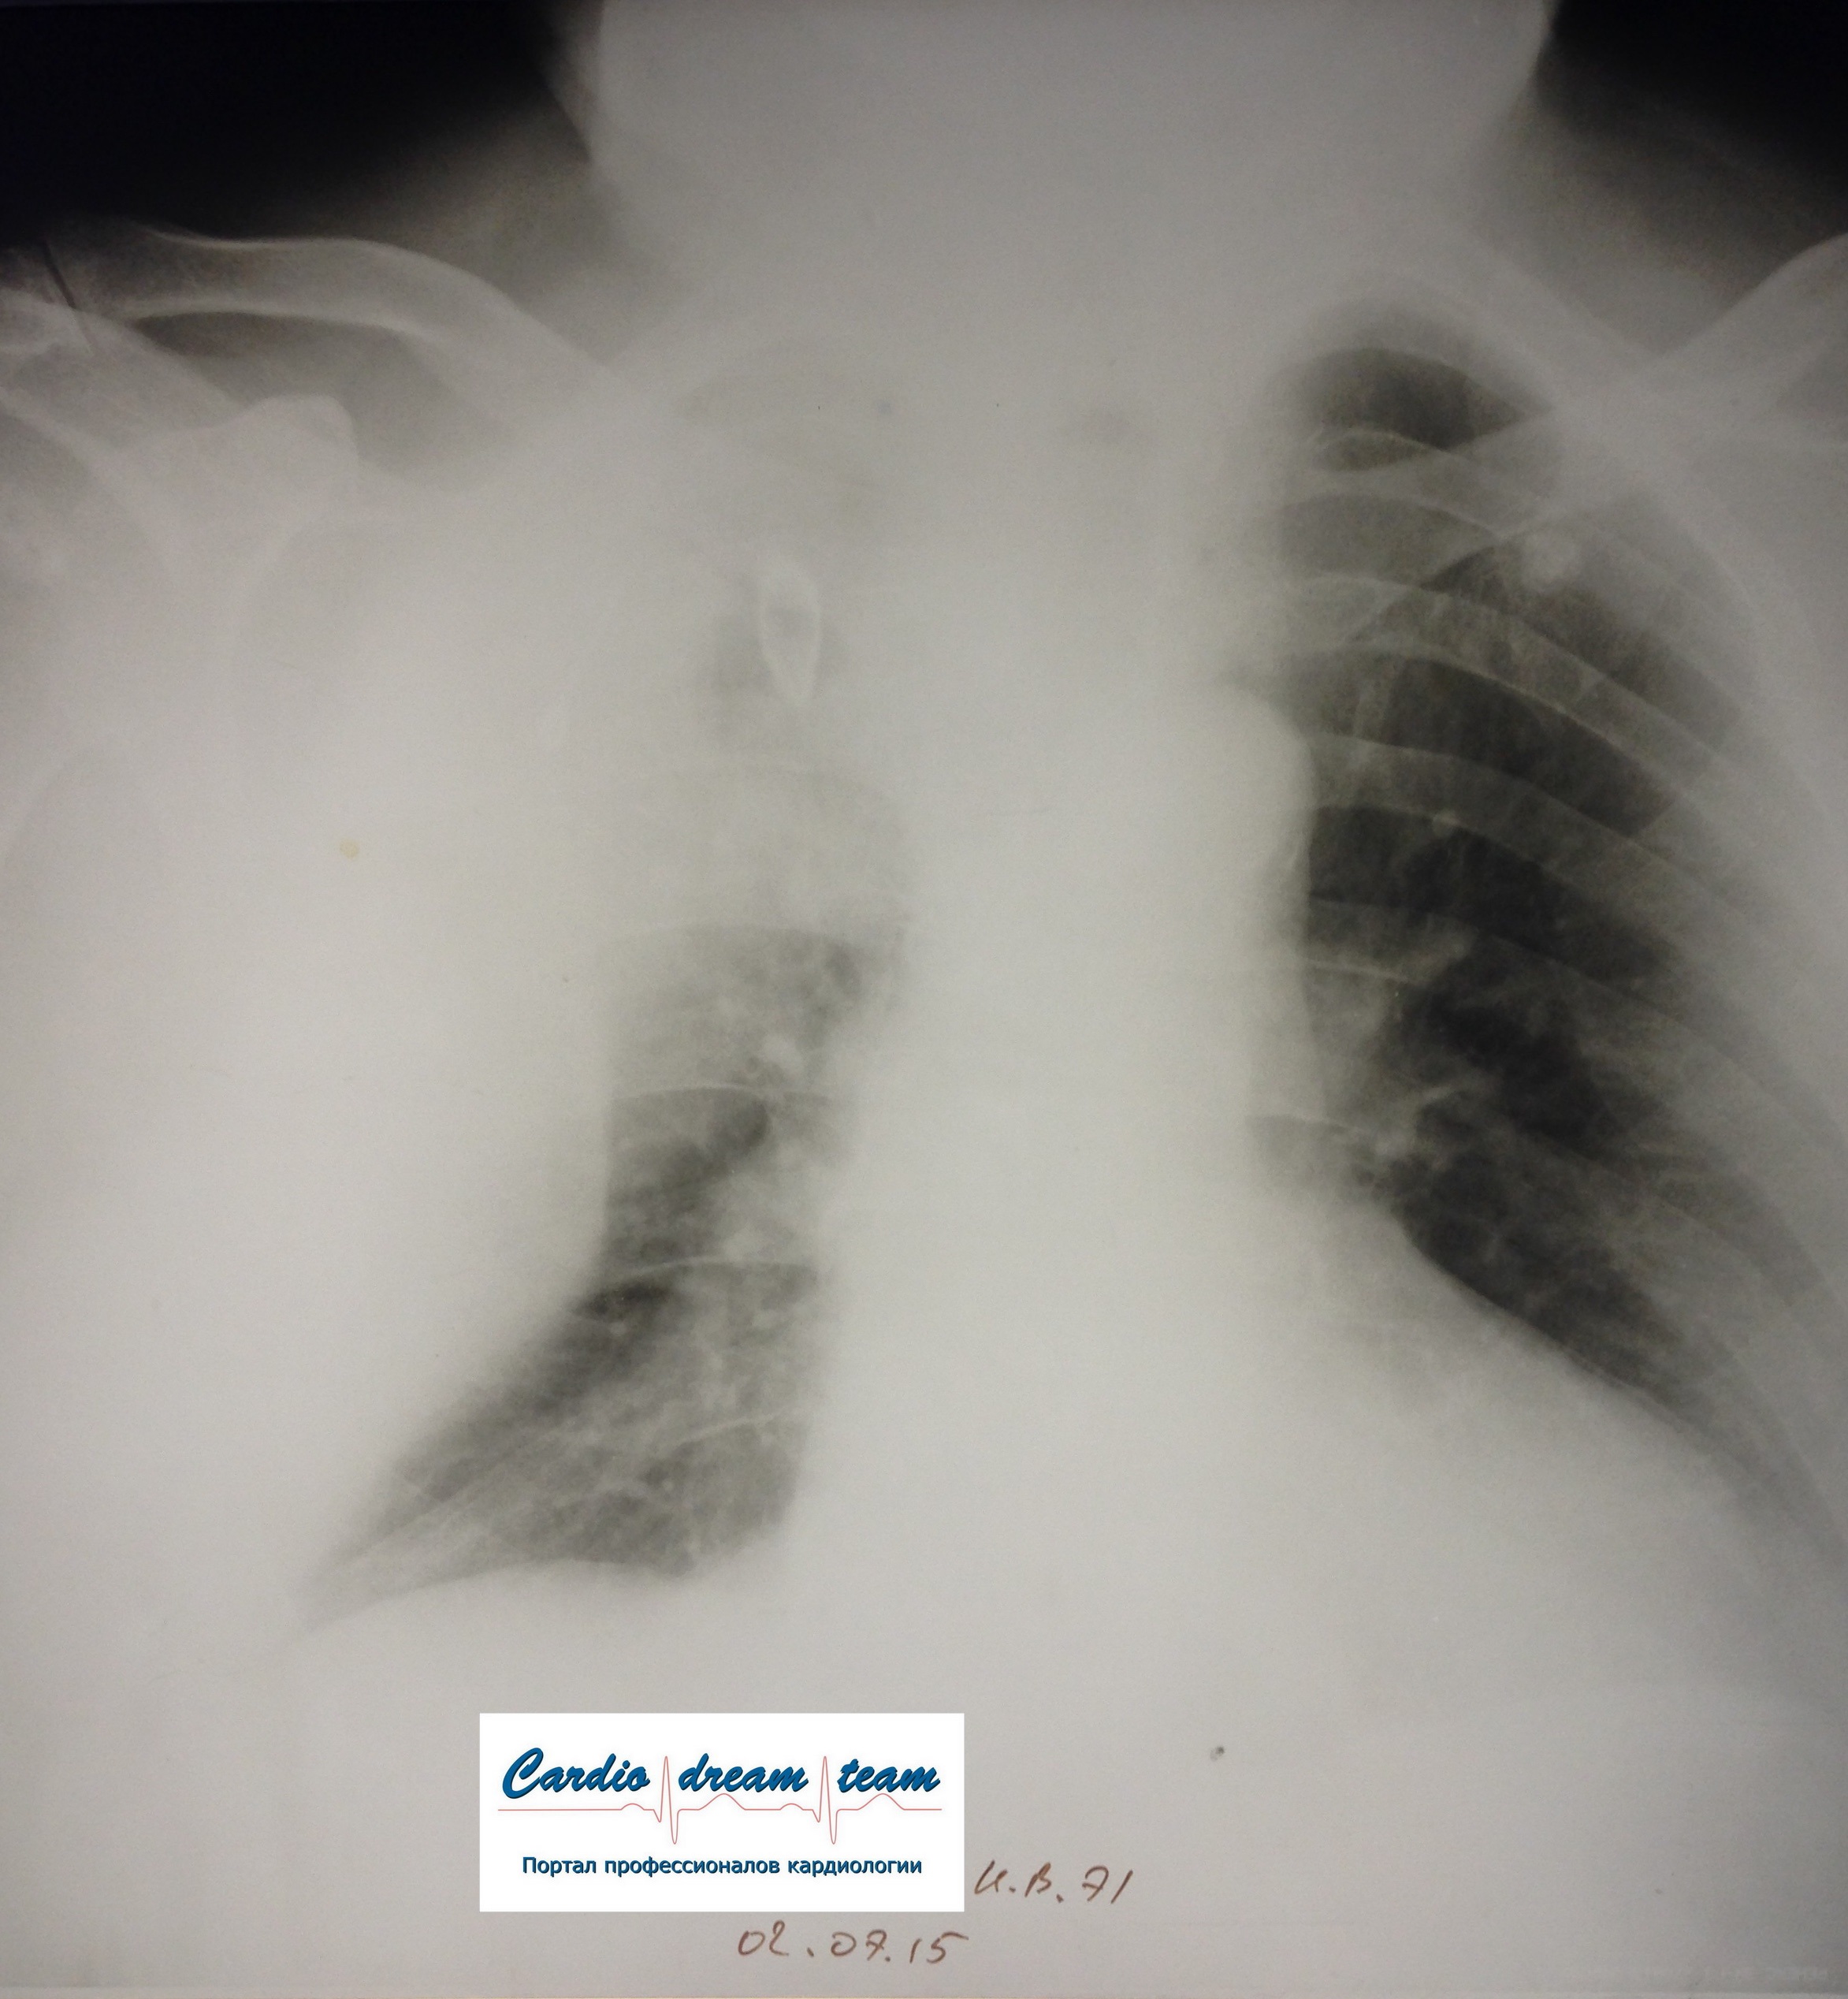

M, 71.

FullSizeRender.jpg

FullSizeRender.jpg [ 895.37 KiB | Просмотров: 17595 ]